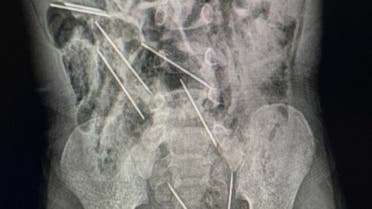

طفل يبتلع 8 إبر حقن لتطعيم الحيوانات

أنقذ أطباء في شمال شرقي بيرو حياة طفل، عمره عامان، بعد أن ابتلع 8 إبر حقن وهو يلعب.

وقال الطبيب إفراين سالاسار: “عندما كنا في غرفة العمليات وفتحنا بطنه وجدنا تلك القطع المعدنية، وأدركنا أنها كانت في الحقيقة إبراً”.

وذكرت وسائل إعلام محلية أن الإبر كانت من تلك التي تستخدم لتطعيم حيوانات بمزرعة تعمل فيها والدة الطفل.